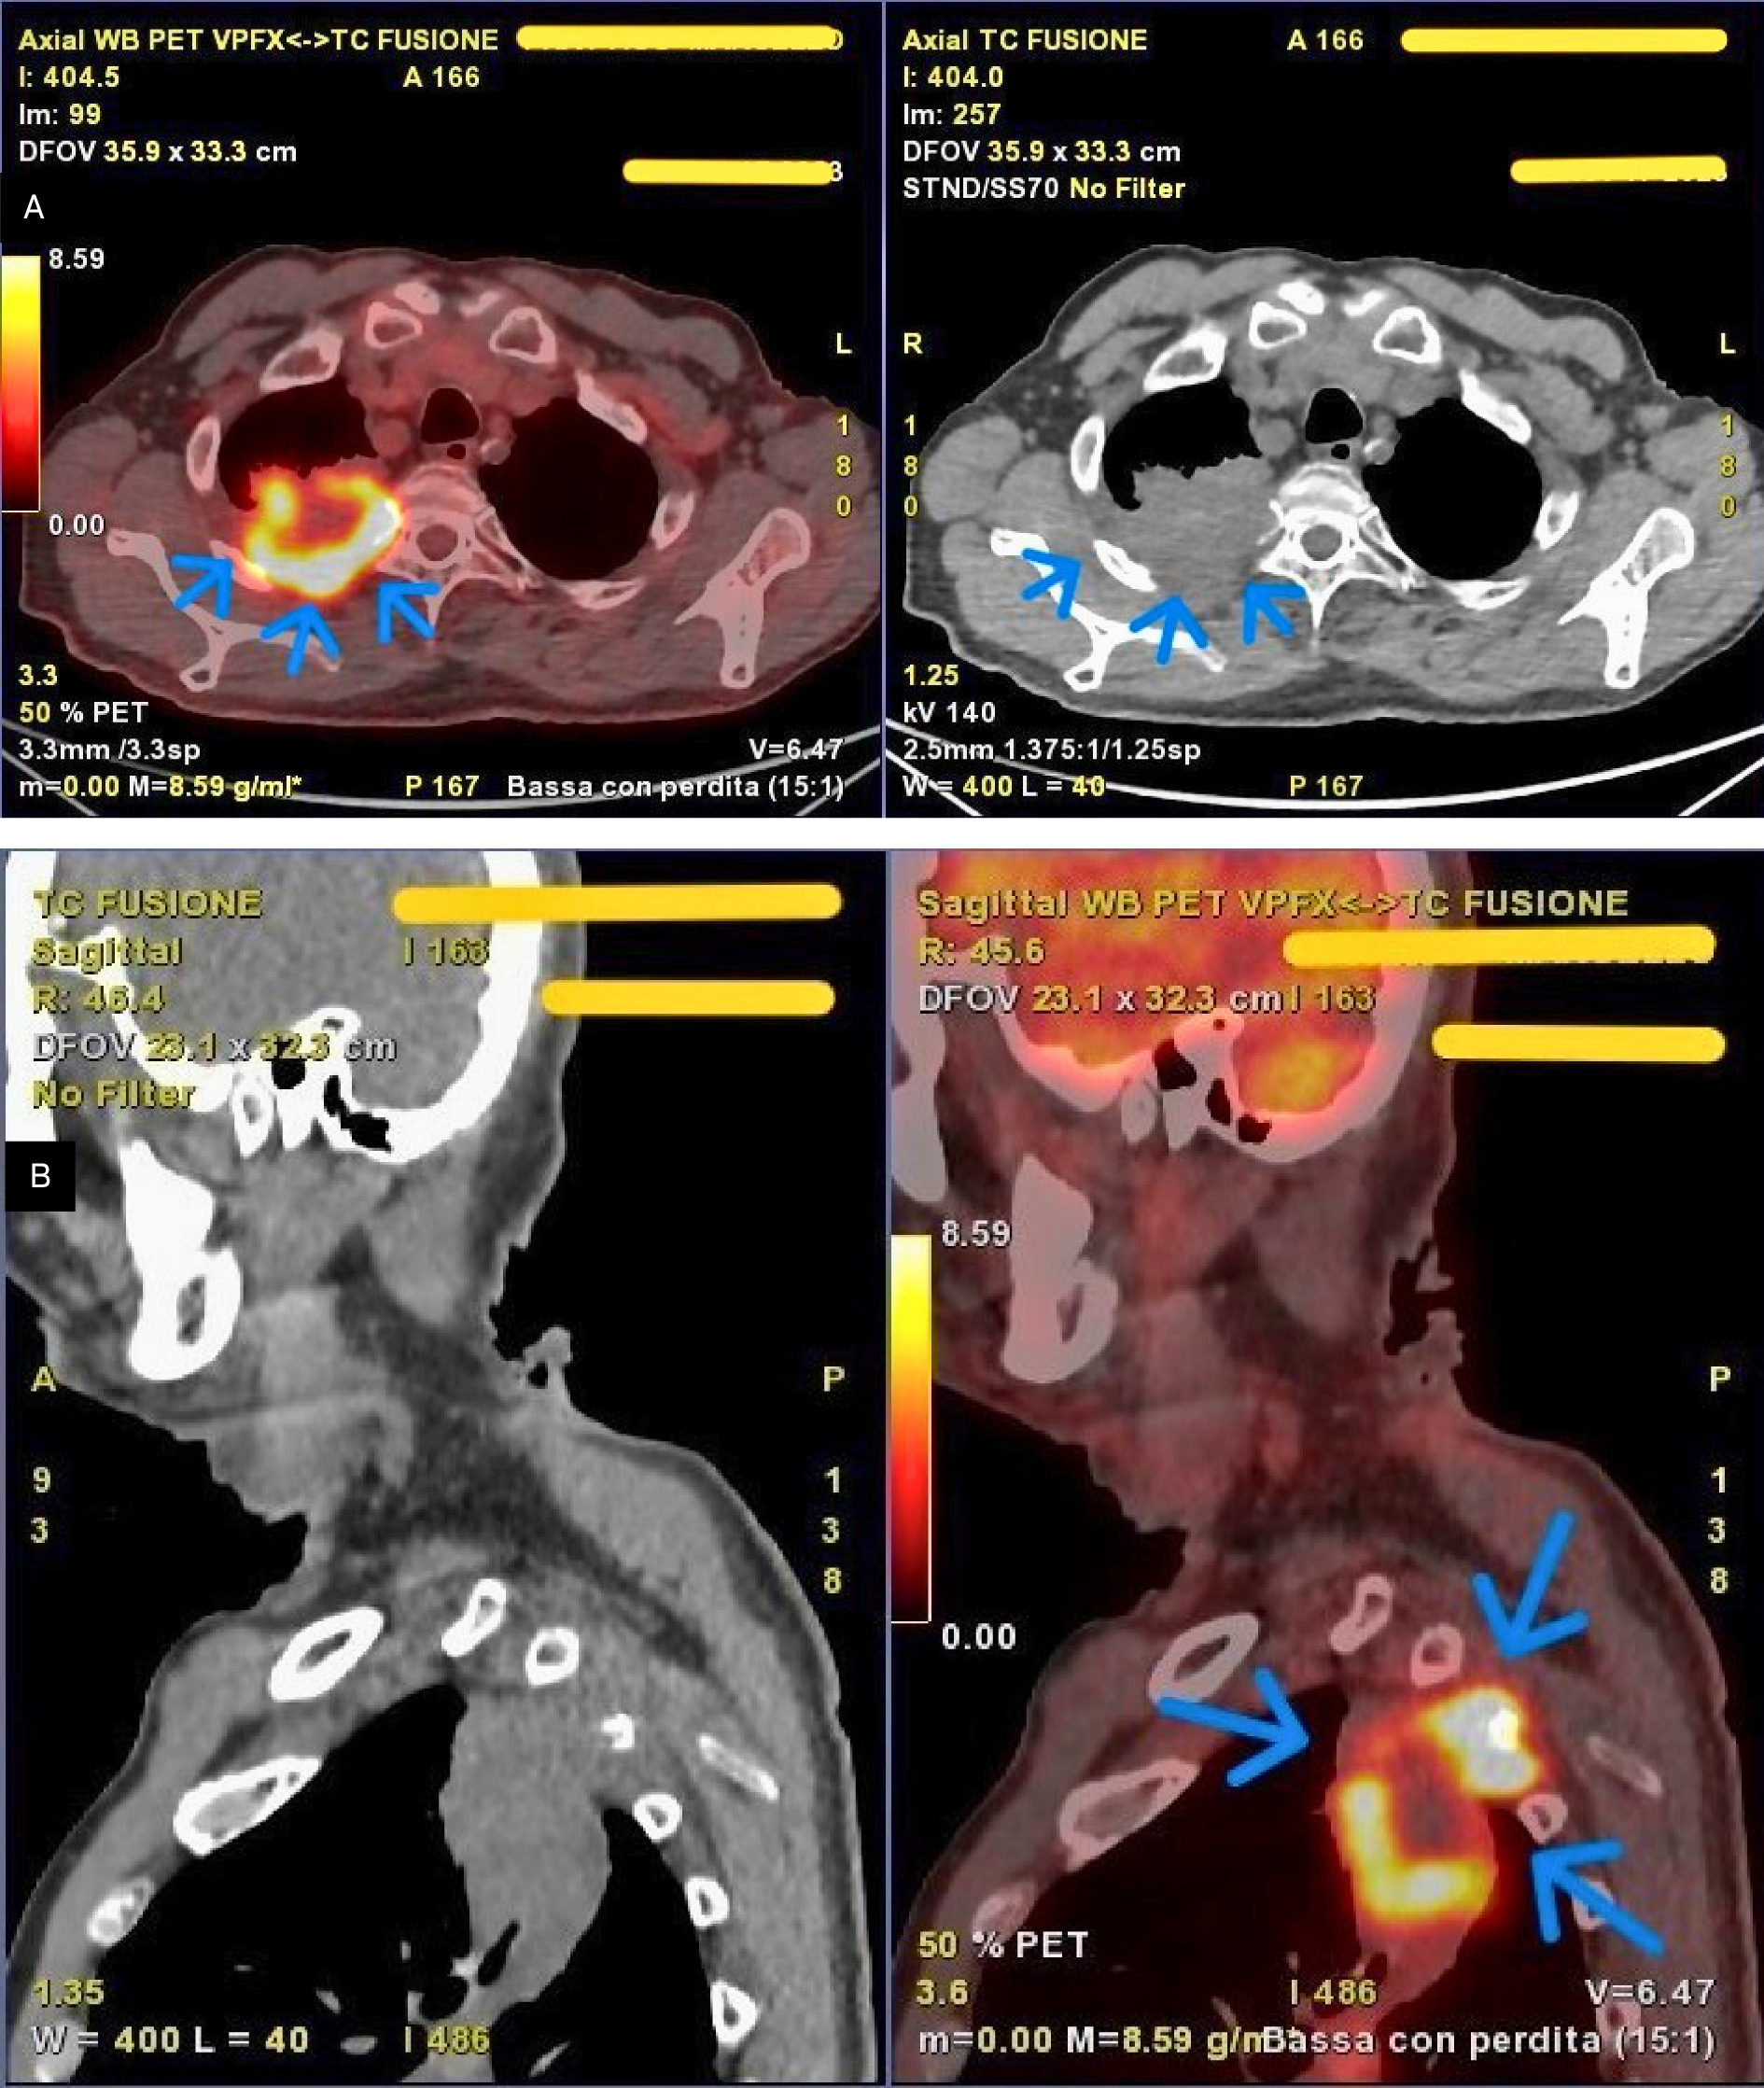

Subsequent whole-body PET (Figure 2A and B) demonstrated intense uptake of fluorodeoxyglucose (SUV_max 19.6) corresponding to the known pulmonary mass, measuring 7.8 cm (axial) × 5.0 cm (coronal) × 9.0 cm (sagittal), located in the apical and posterior segments of the right upper lobe. Moderate tracer uptake suggestive of nodal involvement was observed in the right hilar (SUV_max 3.6) and subcarinal (SUV_max 2.8) regions.